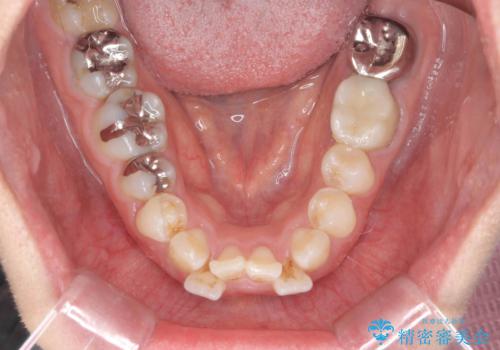

前歯の角度を改善するマウスピース矯正

- 前歯の角度・重なりの改善を求めて矯正治療を希望され来院されました。

しっかりと拡大を行い、IPRも併用したことで歯並びと前歯の角度を大幅に改善することができました。